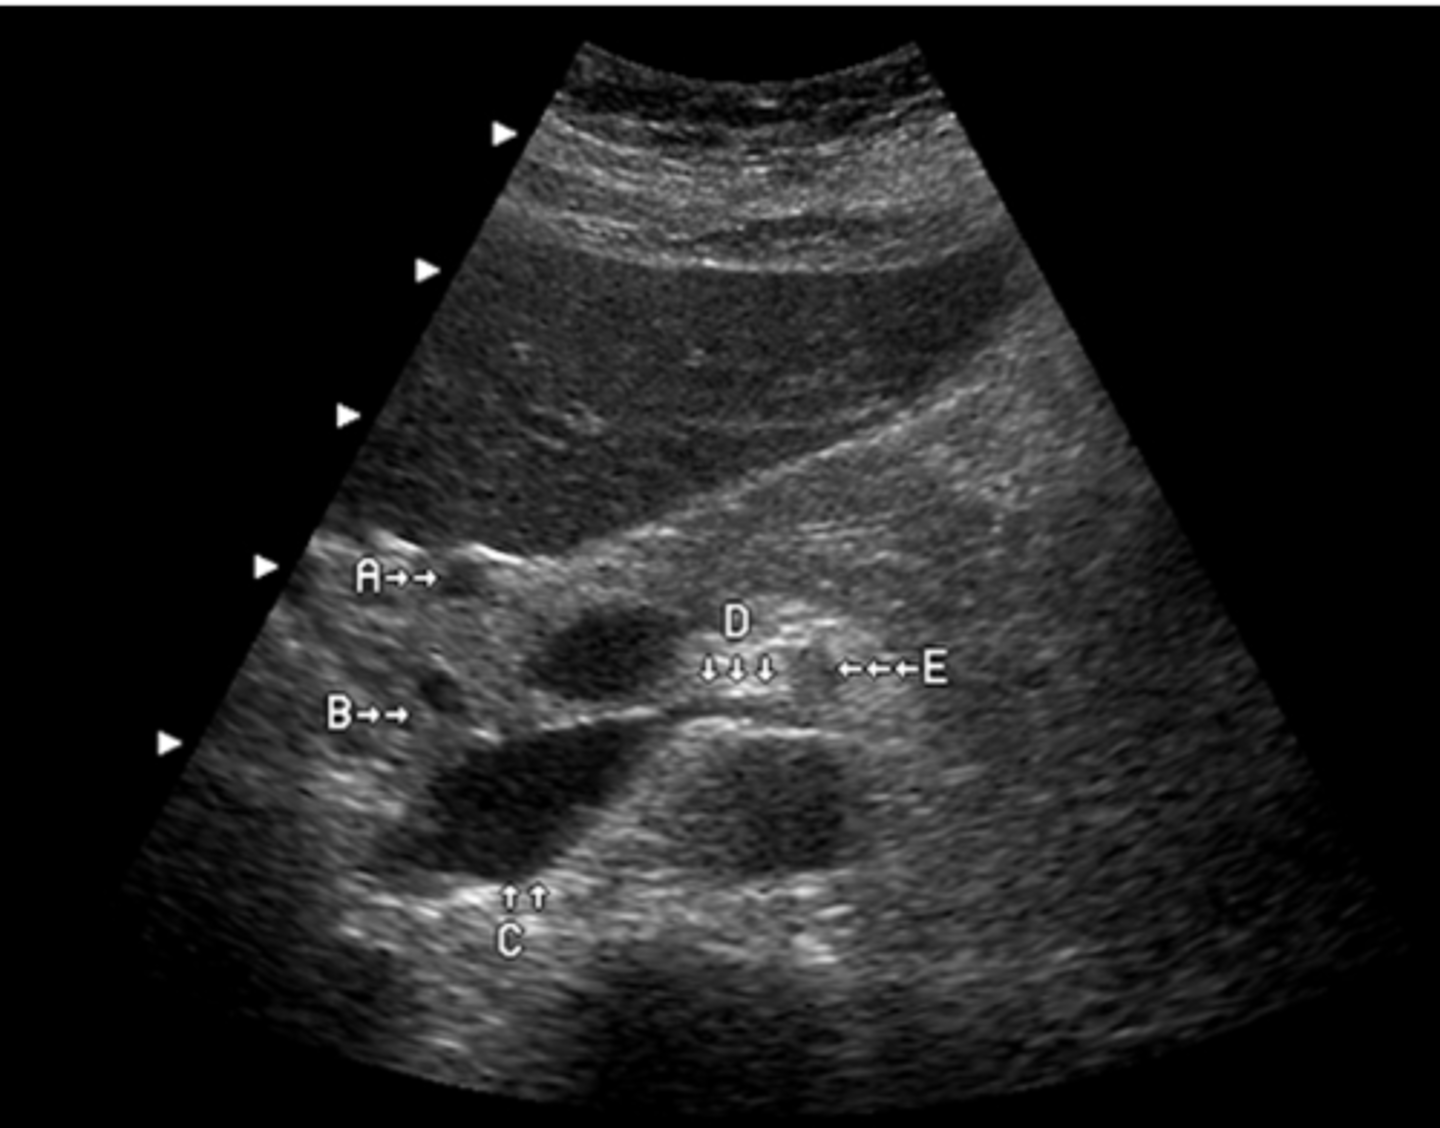

e. splenic cysts

This patient was regerred for an abdominal ultrasound because of epigastric pain and tenderness. This image was obtained from the left upper quadrant. Which of the following describes the ultrasound findings?

a. pleural effusion

b. splenomegaly

c. ascites

d. splenic metastases